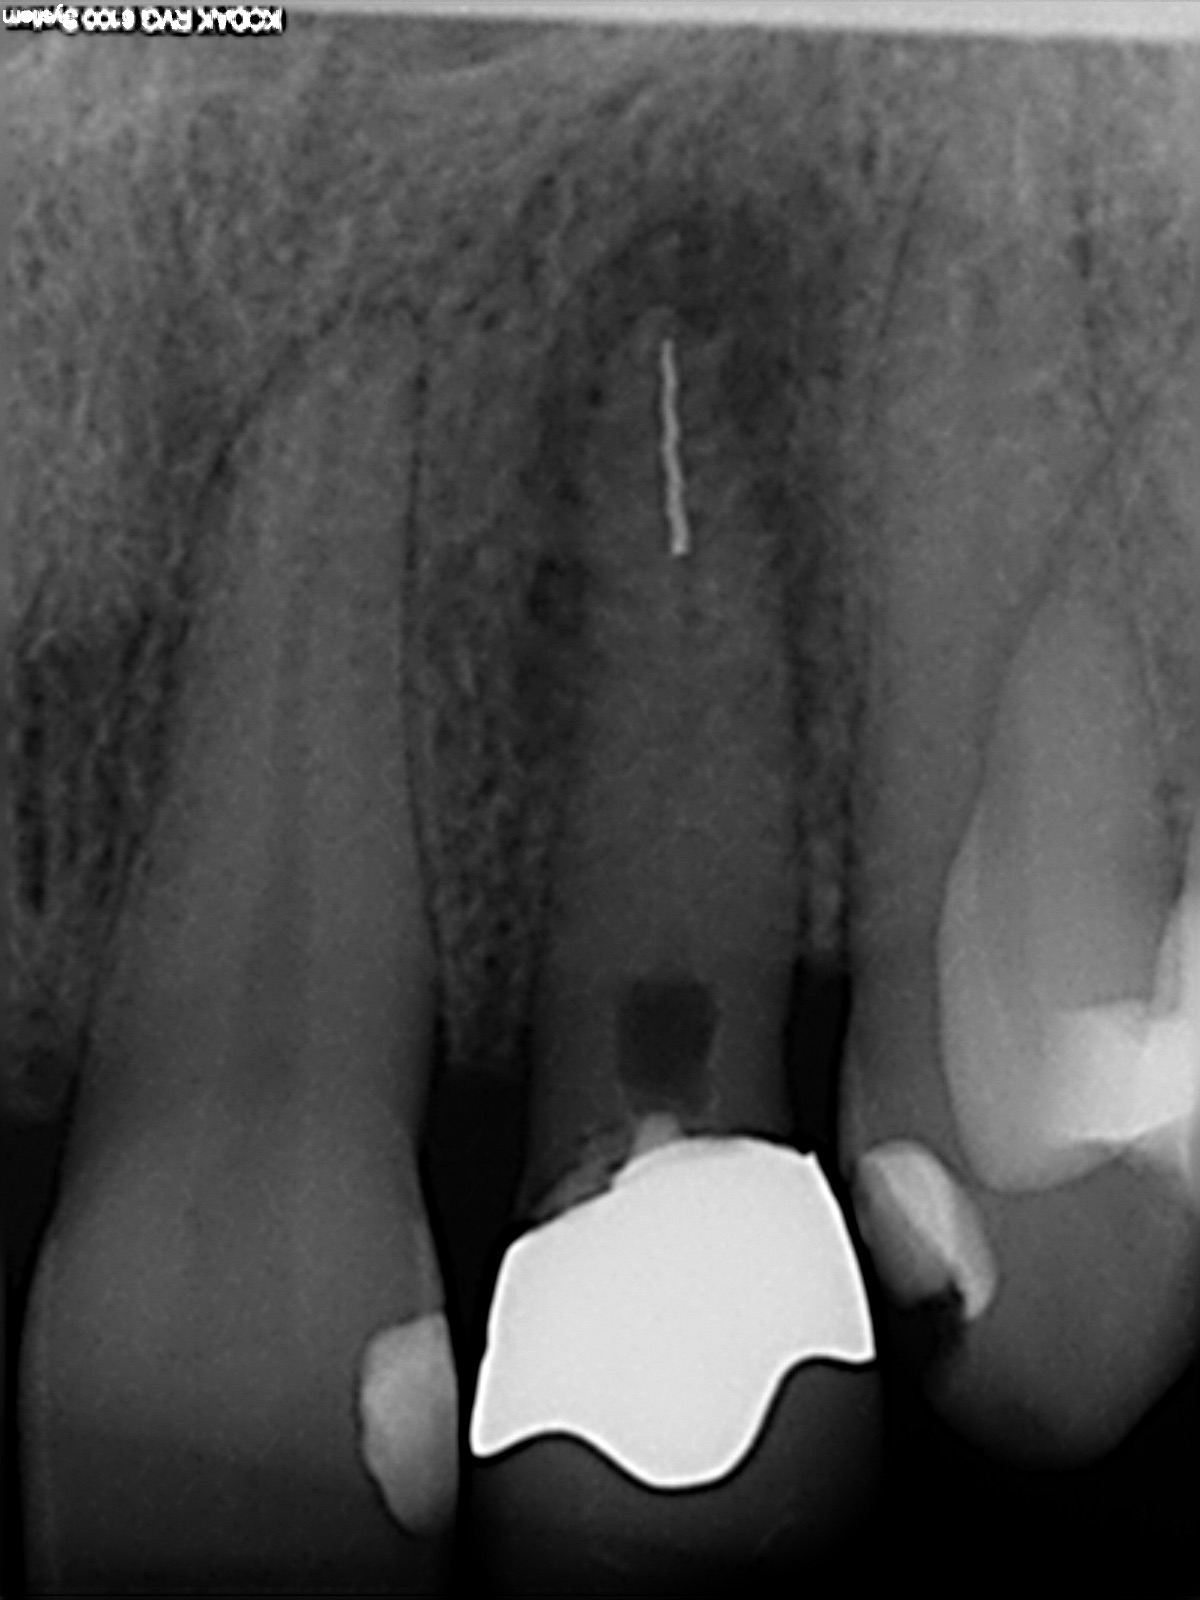

Instrumentenfraktur

Ausgangssituation